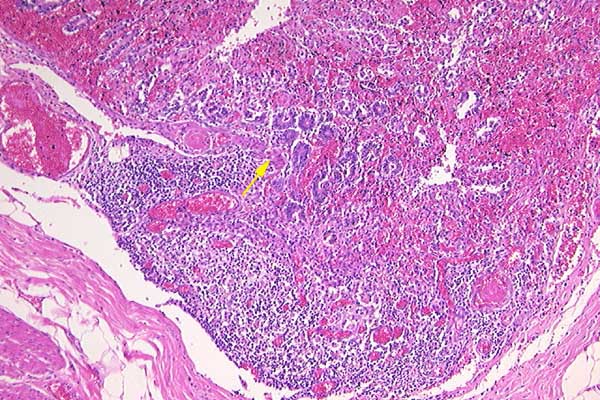

Submucosal lymphoid tissue is depleted. Focally the remaining crypts herniate through the muscularis mucosa (arrow).